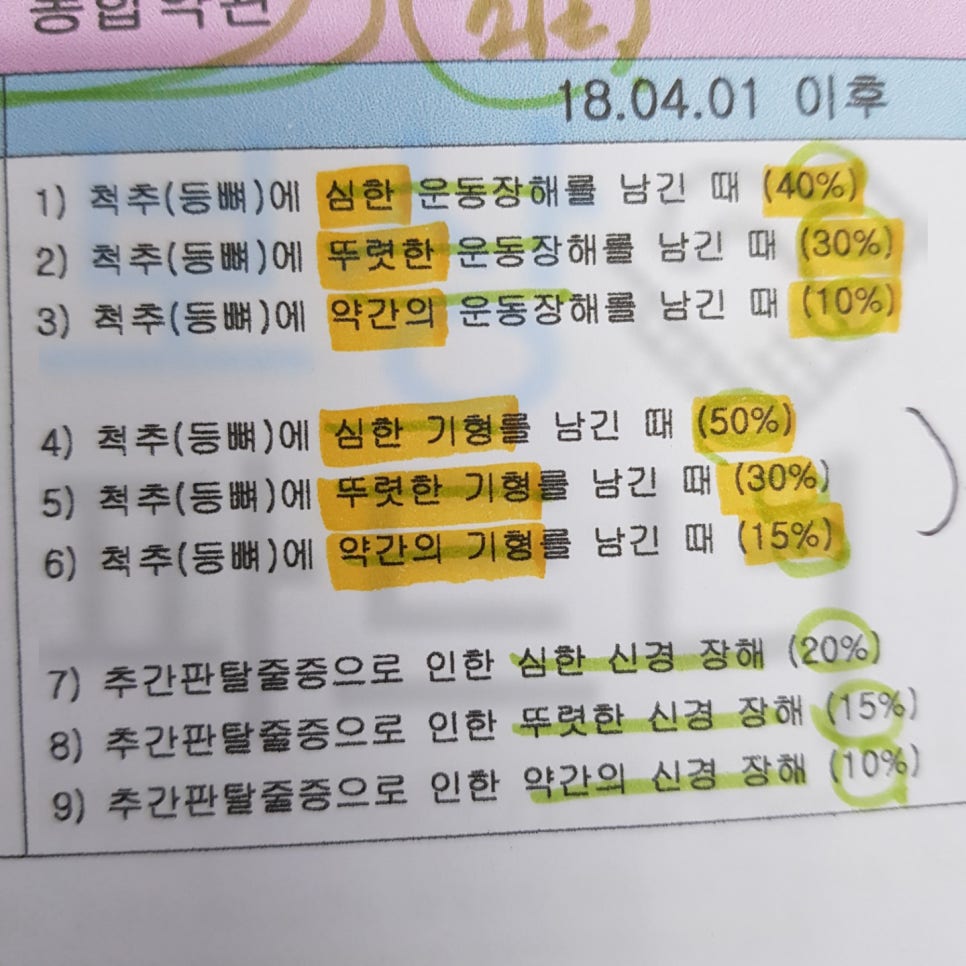

또 개인적으로 가입한 보험의 후유장해의 약관을 보시면 아래의 같은 지급률도 보험금이 지급됩니다.